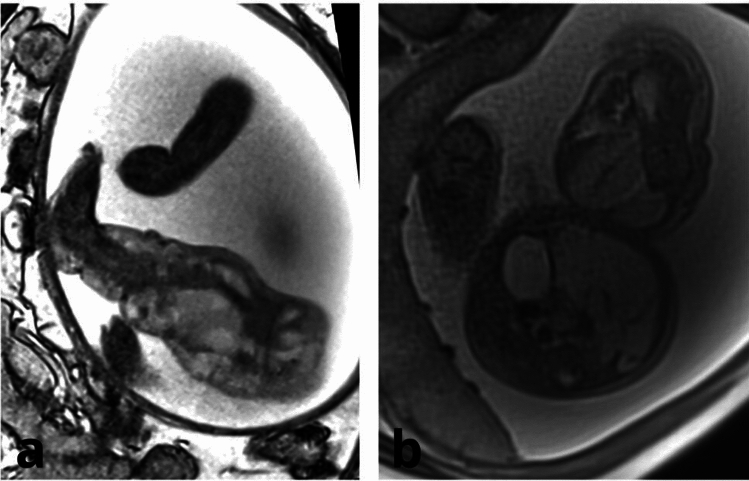

Case reports: Here we report two cases of effective prenatal and postnatal sirolimus treatment of extensive, complicated fetal CLVMs. The CLVMs were diagnosed prenatally by ultrasound and confirmed by magnetic resonance. The pregnancies were complicated with intralesional bleeding in both cases and polyhydramnios in one. The pregnant women received oral sirolimus from the 32nd and 33rd weeks of gestation to delivery (for 11 and 31 days, respectively). The dose of oral sirolimus for the pregnant women ranged from 2 to 6 mg/day, with a target trough whole-blood level of 7-12 ng/mL, which resulted in the umbilical cord arterial blood levels of 3.8 and 6.4 ng/mL, respectively. Therapeutic effects of prenatal sirolimus were observed in both fetuses: one experienced reduced intralesional bleeding, while the other had a significant decrease in CLVM size. The sirolimus treatment has been continued postnatally in both children, currently aged 20 and 9 months. The mothers and children experienced no adverse events from the treatment.